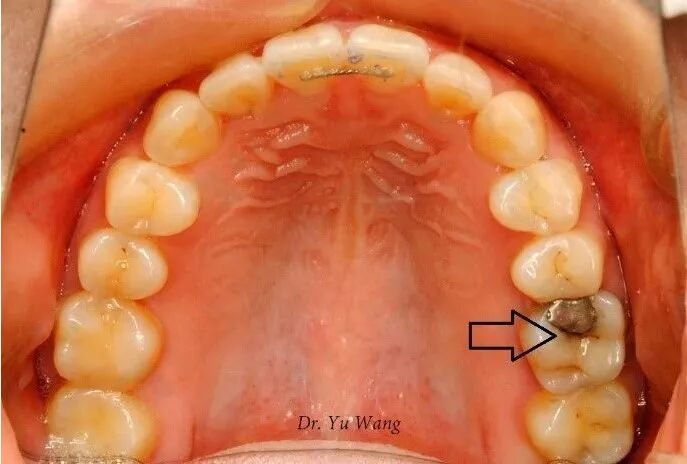

4.某些牙科治疗:汞合金修复体(银汞填充物),特别是含硫化银的材料,可能导致牙齿变黑,使牙齿呈灰黑色。

银汞充填物边缘发黑